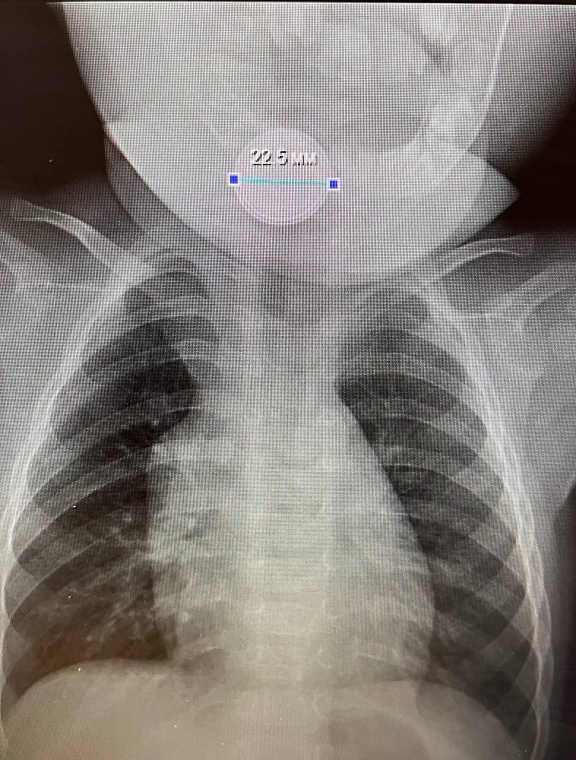

В приемное отделение областной больницы №14 в селе Казанское поступил девятимесячный малыш с инородным телом в пищеводе. Мама сообщила, что ребенок кашляет, у него шумное дыхание. Оказалось, что он проглотил батарейку.

Как сообщает региональнй Информационный центр, операцию провели врач хирург-эндоскопист Мыктыбек Тажибаев, врач анестезиолог-реаниматолог Игорь Пак, медицинская сестра кабинета эндоскопии Наталья Плесовких и медицинская сестра-анестезист Елена Тимофеева. Ребенок находился под общим наркозом. Операция прошла успешно. Батарейка не успела навредить желудку. Малыш выписан из больницы.

Фото: Информационный центр Тюменской области